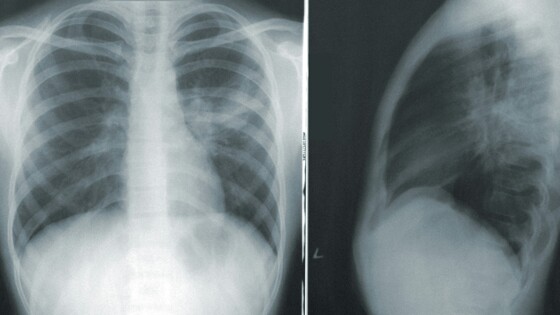

Симптомы онкологии легких не проявляются на ранних стадиях, рак можно выявить только при профобследовании, рассказал заведующий отделением торакальной онкологии № 1 Московского областного онкодиспансера Сергей Тараров.

"Ежегодно в Московский областной онкологический диспансер поступает более 1 тыс. пациентов с раком легких. Проблема в том, что на начальной стадии у злокачественных опухолей легких нет никаких симптомов. Выявить их можно только при профилактическом обследовании. Поэтому необходимо отказаться от курения, чаще бывать на свежем воздухе, вести активный образ жизни, заниматься спортом, контролировать уровень стресса и психологических нагрузок", - приводит слова Тарарова пресс-служба министерства здравоохранения Подмосковья.

В пресс-службе отметили, что рак легких занимает одно из лидирующих мест среди онкологических заболеваний по распространенности и смертности. При отсутствии должного лечения опухолевый процесс может распространиться за пределы легкого, поражая другие органы.

Специалисты Московского областного онкологического диспансера напомнили, что выявление заболевания на ранней стадии эффективнее поддается лечению, поэтому необходимо регулярно проходить профосмотры и диспансеризацию.